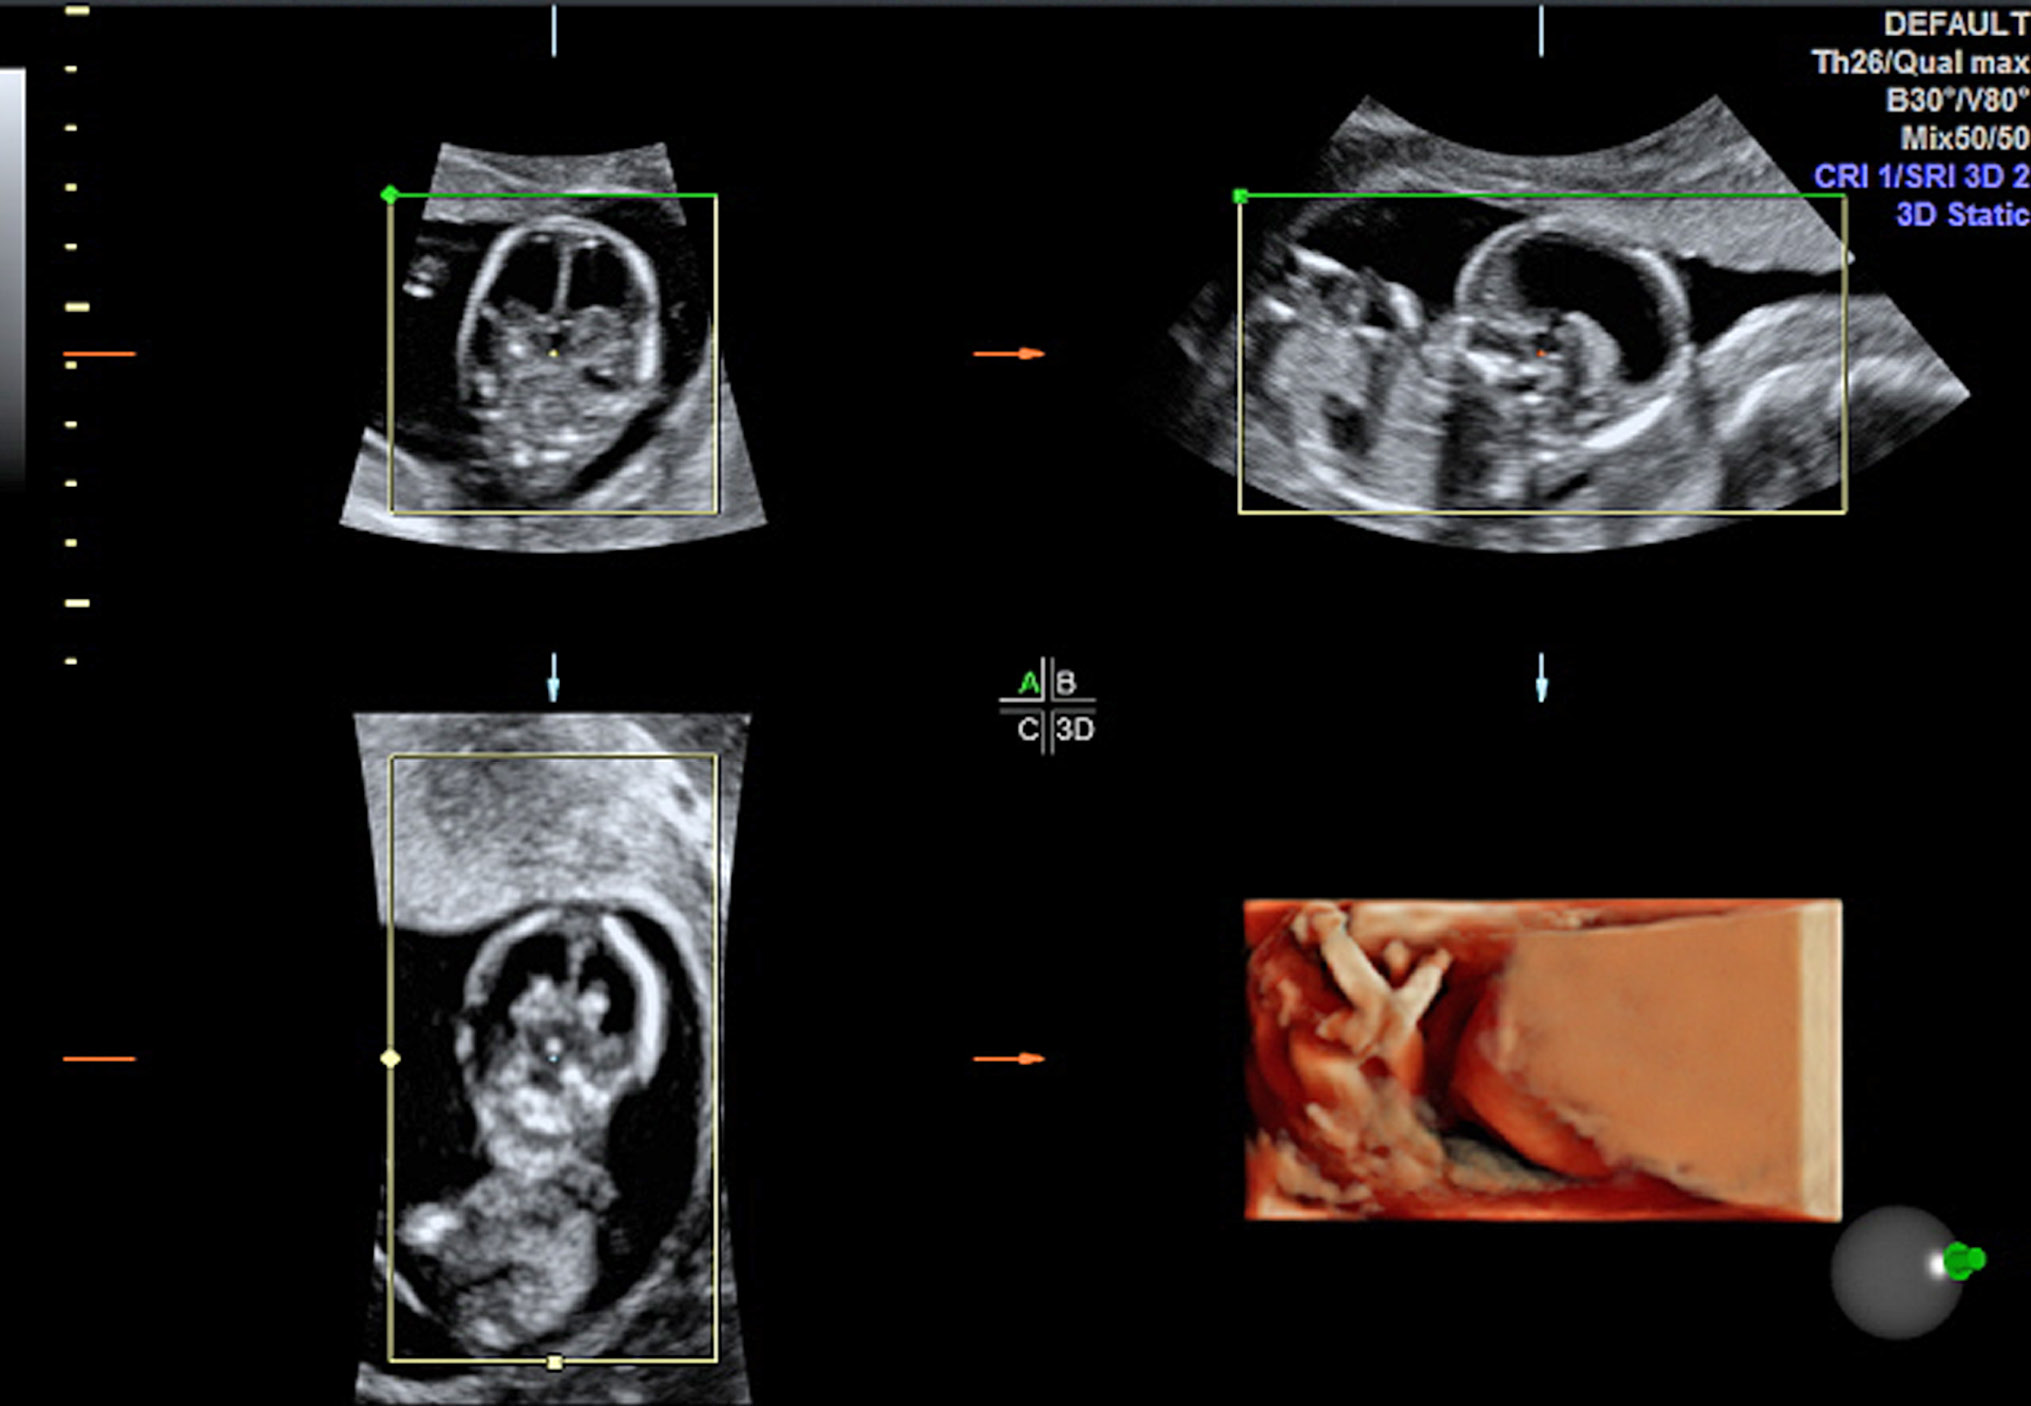

Рис. 1. Эхограмма 3D/4D. Режим VOCAL. Беременность 14–15 нед. Подтвержденный врожденный порок развития плода: аутосомно-рецессивная поликистозная болезнь почек. Контур зоны интереса (желтая линия) и автоматическое получение объема максимального кармана околоплодных вод. Объем максимального кармана околоплодных вод — 6,5 см3 (маловодие). А, B, С — три взаимно перпендикулярные плоскости определения объема максимального кармана околоплодных вод. D — объемная модель максимального кармана околоплодных вод

Fig. 1. Echogram 3D / 4D. VOCAL mode. Pregnancy 14-15 weeks. Confirmed congenital malformation of the fetus: autosomal recessive polycystic kidney disease. Contour of the zone of interest (yellow line) and automatic acquisition of the volume of the maximum pocket of amniotic fluid. The volume of the maximum pocket of amniotic fluid is 6.5 cm3 (lack of water). A, B, C - three mutually perpendicular planes for determining the volume of the maximum pocket of amniotic fluid. D - volumetric model of the maximum pocket of amniotic fluid